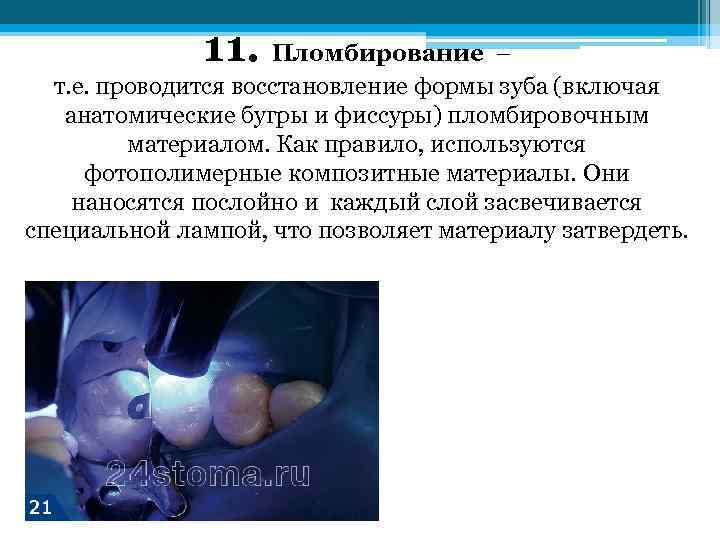

11. Пломбирование – т. е. проводится восстановление формы зуба (включая анатомические бугры и фиссуры) пломбировочным материалом. Как правило, используются фотополимерные композитные материалы. Они наносятся послойно и каждый слой засвечивается специальной лампой, что позволяет материалу затвердеть.

11. Пломбирование – т. е. проводится восстановление формы зуба (включая анатомические бугры и фиссуры) пломбировочным материалом. Как правило, используются фотополимерные композитные материалы. Они наносятся послойно и каждый слой засвечивается специальной лампой, что позволяет материалу затвердеть.